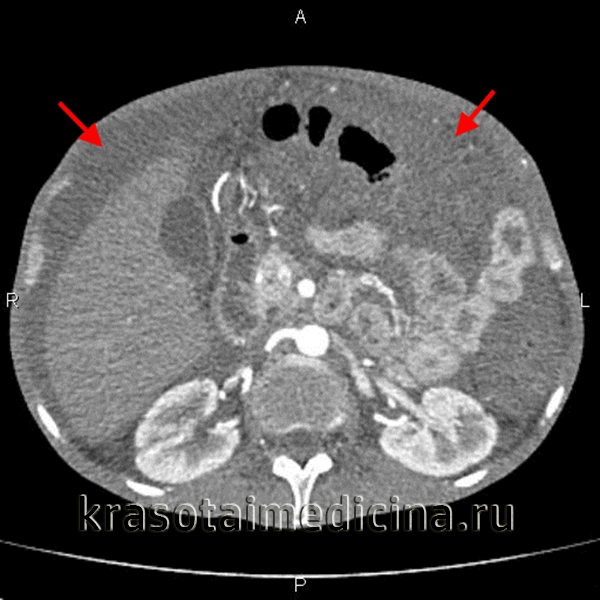

(Слева) На аксиальной КТ с контрастом определяются отграниченные скопления жидкости со сложной структурой, являющиеся результатом желчного перитонита из-за повреждения билиарного тракта. Визуализируется жидкость в малом брюшинном мешке, которая смещает желудок и двенадцатиперстную кишку обычно жидкость здесь скапливается в результате других причин (панкреатит, язва желудка), перитонита, канцероматоза.

(Справа) На аксиальной Т1 МР томограмме с жироподавлением и контрастным усилением определяется отграниченный асцит BE в полости таза. Обратите внимание на выраженное утолщение брюшины и повышенное накопление контраста (больше в задних отделах) при канцероматозе брюшины.

(Слева) На аксиальной КТ с контрастным усилением определяется выраженное утолщение дистальных отделов желудка, которое может быть обусловлено злокачественным новообразованием. Выраженный асцит сочетается с узловым утолщением париетальной брюшины что является признаком злокачественной природы асцита в результате первичного рака желудка.

(Справа) На аксиальной КТ с контрастом у этого же пациента визуализируется опухоль, распространяющаяся по ходу желудочно-ободочной связки, и поражающая поперечную ободочную кишку. Обратите внимание на локальное узловое утолщение париетальной брюшины. Опухоли ЖКТ часто становятся причиной «злокачественного» асцита у мужчин.